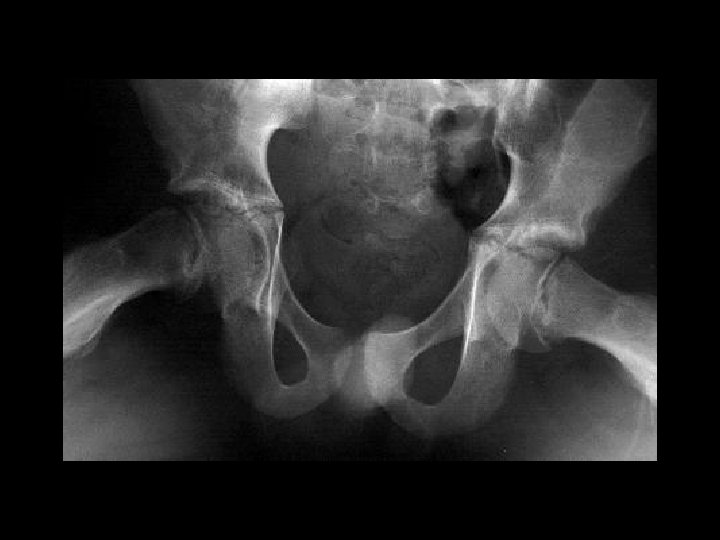

Femoral Head AVN • Findings: – bilateral femoral head AVN w/o collapse – right pelvic renal tx